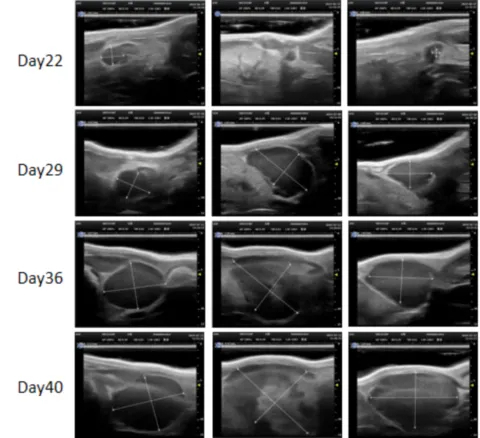

PDX Model (Growth Curve)

部分不朽情缘mg官网PDX原位模型展示